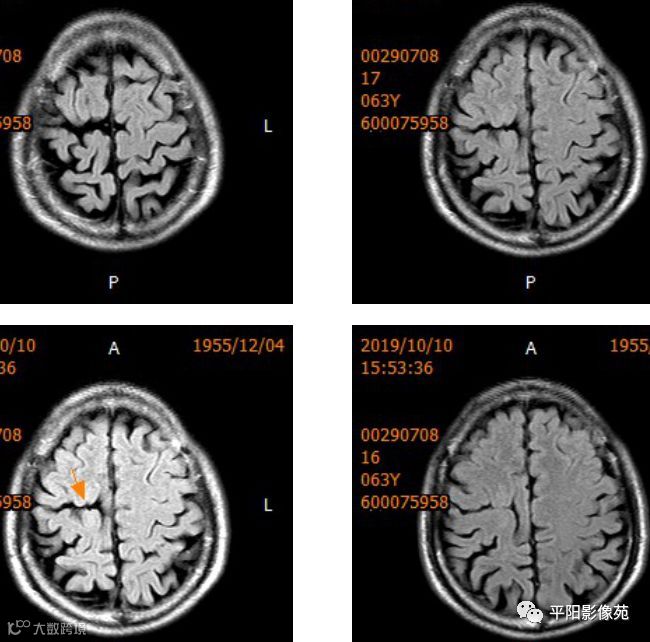

右侧额叶中央前回局部脑裂增宽,并向内延伸,周围衬以等灰质信号,呈稍长T1稍长T2信号,病灶自软脑膜向内延伸,与室管膜相连。